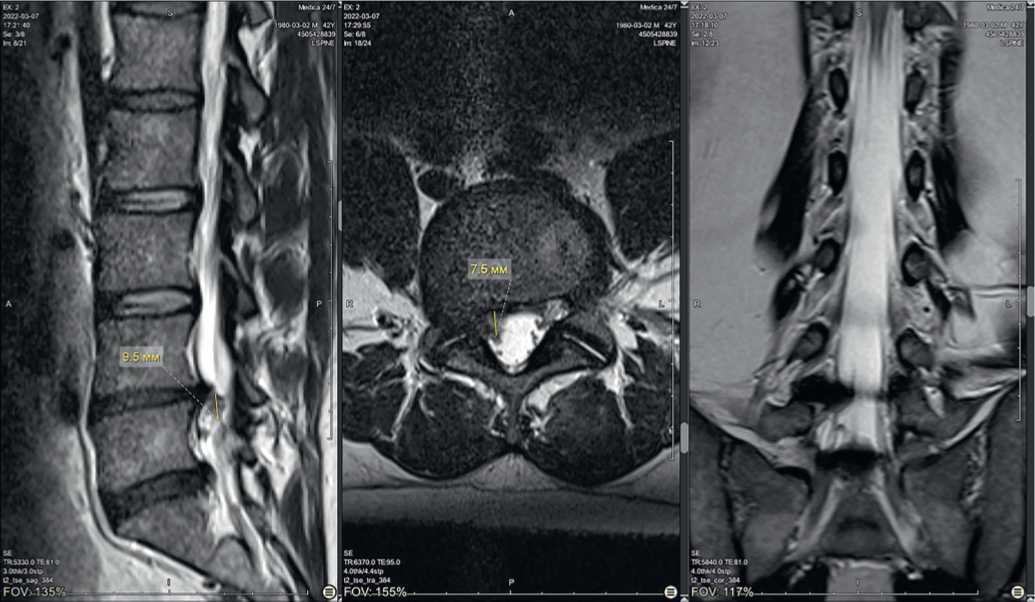

На контрольной МРТ от 17.04.2022 определяется дальнейшее уменьшение глубины грыжевого выпячивания до 5,8 мм, распространение в позвоночном канале краниокаудально прежнее — 9,2 мм (рис. 4).

Рис. 4. Магнитно-резонансная томограмма пациента К. на фоне лечения 17.04.2022 г.: A) саггитальный срез, B) аксиальный срез на уровне межпозвонкового диска L4-L5, C) фронтальный срез

Рис. 4. Magnetic resonance imaging of patient K. during treatment on 17.04.2022: A) sagittal section, B) axial section at the level of the intervertebral disc L4-L5, C) frontal section

После курса акупунктуры при контрольной МРТ от 17.06.2022 отмечена выраженная положительная динамика: секвестр не определяется (обратное развитие), размеры грыжевого выпячивания значительно уменьшились (уменьшение глубины грыжевого выпячивания до 5,8 мм), признаки компрессии корешка не определяются (рис. 5).

Рис. 5. Магнитно-резонансная томограмма пациента К., саггитальный срез: A) исходная, B) после лечения 17.06.2022

Fig. 5. Magnetic resonance imaging of patient K., sagittal section: A) initial, B) after treatment 06.17.2022